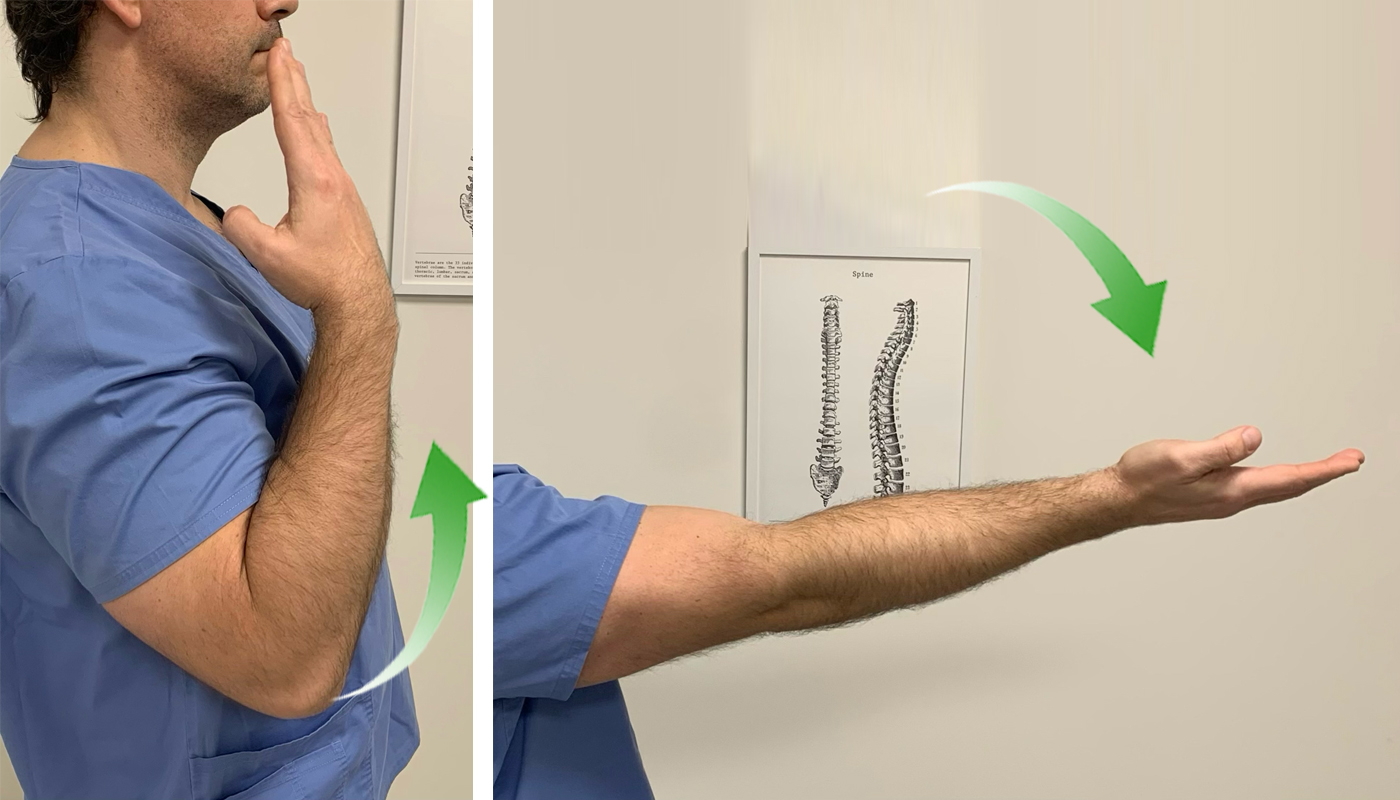

2. Pronación- supinación

La pronosupinación consiste en el movimiento de rotación que realiza la mano respecto al eje longitudinal del antebrazo. Nos permite colocar la palma de la mano mirando hacia el techo o hacia el suelo.

Este movimiento involucra tanto la articulación del codo como la de la muñeca.

Realizamos movimientos de pronación y supinación de codo de forma lenta y llevando la articulación al rango máximo de movilidad que podamos activamente y sin provocar dolor.

1. Nervio Mediano:

Vamos a realizar, primero, una puesta en tensión y estiramiento del nervio para después pasar a una movilización.

Partimos de una posición erguida de pie o sentado. Colocamos el brazo del lado que queremos trabajar en separación lateral de unos 90º, con la palma de la mano mirando hacia arriba. Vamos a realizar una flexión dorsal de la muñeca y mantenemos el codo extendido.

Para aumentar la tensión, inclinamos lateralmente la cabeza hacia el lado contrario.

De esta manera estamos poniendo en tensión el nervio mediano y podemos sentir la sensación de tensión y cierto hormigueo en el brazo y la mano.

Aguantamos unos segundos en esta posición y pasamos a trabajar el deslizamiento del nervio. Para ello, inclinamos la cabeza hacia el lado afecto (deberemos notar en este momento que desaparece la tensión y el hormigueo). Y ahora volvemos a inclinar la cabeza hacia el lado contrario a la vez que hacemos una flexión palmar de la muñeca. Cuando llegamos al límite de movimiento, inclinamos la cabeza de nuevo hacia el lado afecto y hacemos otra vez flexión dorsal de la muñeca.

El ejercicio consiste en alternar inclinación contraria de la cabeza + flexión palmar de la muñeca y inclinación hacia el lado de la lesión + flexión dorsal.

Realizaremos este ejercicio en 3 series de 10 repeticiones.

2. Nervio Radial

Vamos a realizar, primero, una puesta en tensión y estiramiento del nervio para después pasar a una movilización.

Partimos de una posición erguida de pie o sentado. Colocamos el brazo estirado y pegado a nuestro cuerpo. Seguidamente realizamos una rotación interna del hombro de forma que la palma de la mano quede mirando hacia lateral y el pulgar hacia atrás.

Nos aseguramos de descender el hombro para generar estiramiento entre las cervicales y el hombro.

Hacemos una flexión palmar de la muñeca e inclinamos lateralmente la cabeza hacia el lado contrario. De esta manera estamos poniendo en tensión el nervio mediano y podemos sentir la sensación de tensión y cierto hormigueo en el brazo y la mano.

Aguantamos unos segundos en esta posición y pasamos a trabajar el deslizamiento del nervio. Para ello, inclinamos la cabeza hacia el lado afecto (deberemos notar en este momento que desaparece la tensión y el hormigueo).

Y ahora volvemos a inclinar la cabeza hacia el lado contrario a la vez que hacemos una flexión dorsal de la muñeca. Cuando llegamos al límite de movimiento, inclinamos la cabeza de nuevo hacia el lado afecto y hacemos otra vez flexión palmar de la muñeca.

El ejercicio consiste en alternar inclinación contraria de la cabeza + flexión dorsal de la muñeca e inclinación hacia el lado de la lesión + flexión palmar.